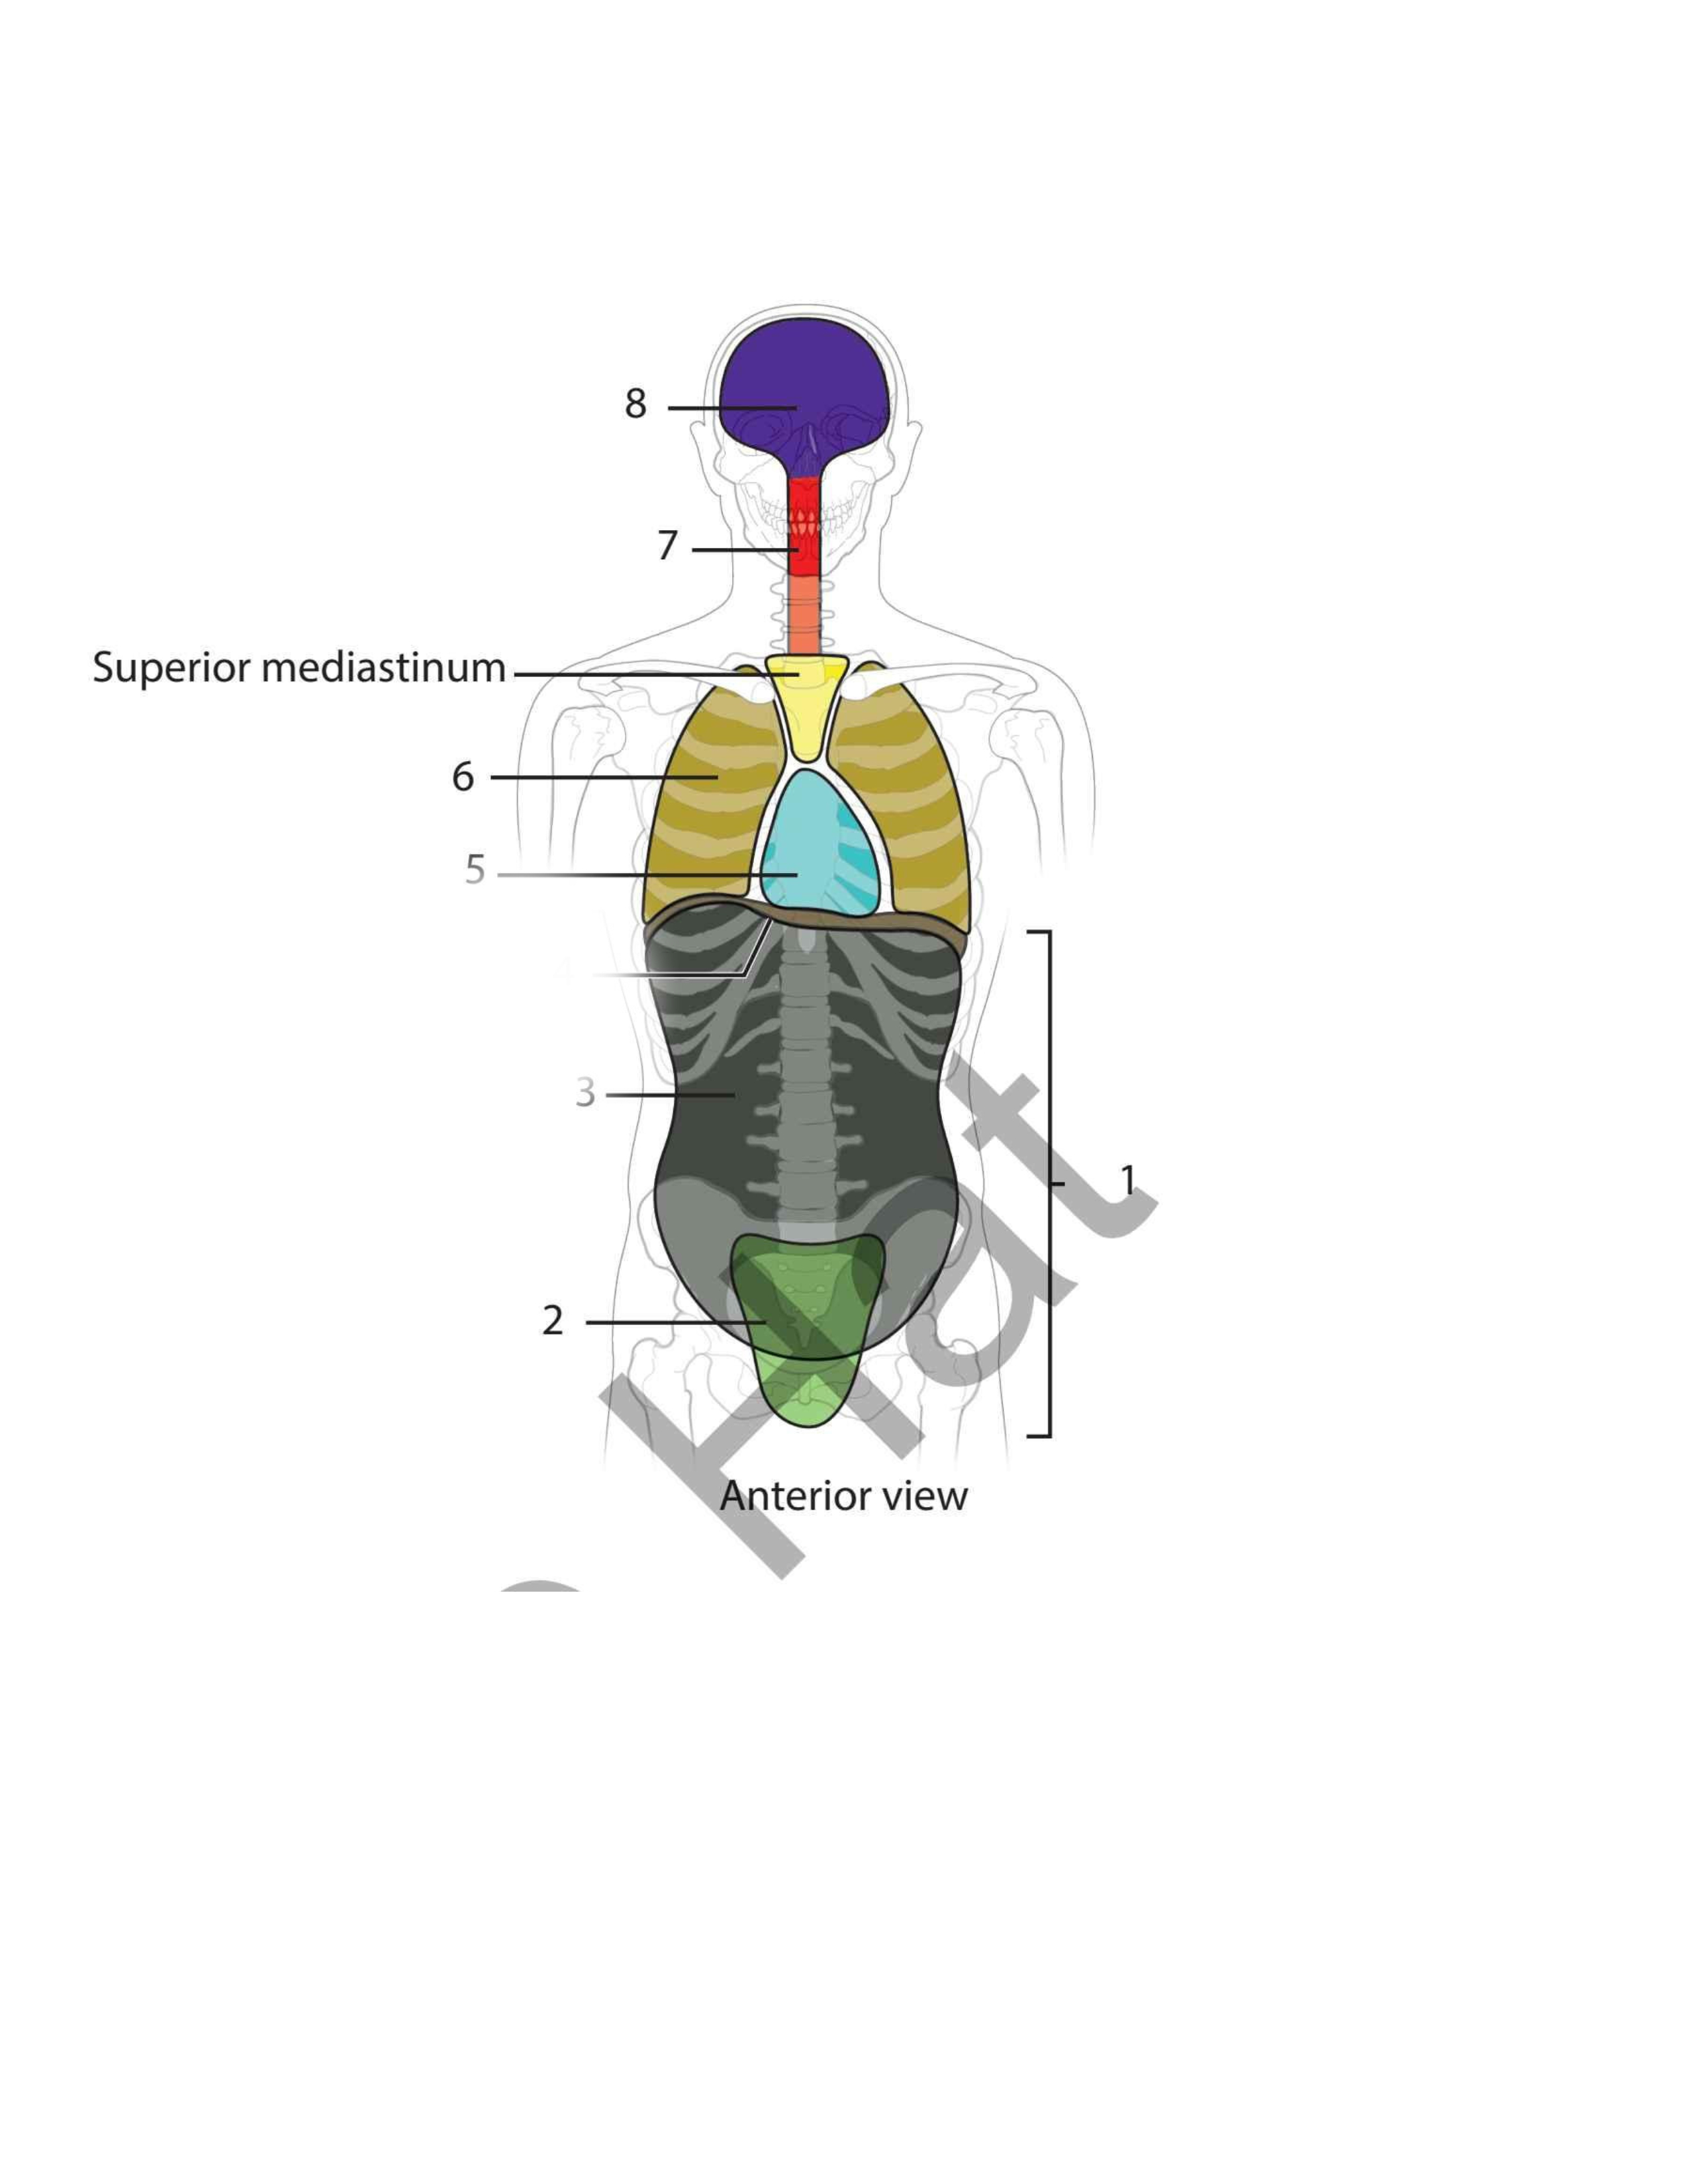

Pelvic

Abdominal

Diaphragm

Pericardial

Pleural

Vertebral

Cranial